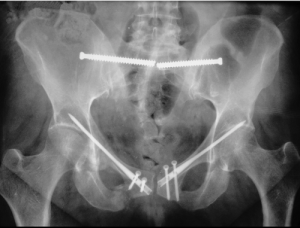

Для фиксации лонного сочленения применяли систему, состоящую из двух блокирующихся транспедикулярных винтов, введенных в вертикальные ветви лонных костей сверху вниз и соединенных между собой металлической штангой. Оценку стояния костных структур и металлоконструкций осуществляли при помощи полипозиционной рентгеноскопии на C-дуге General Electric OEC 9900 Elit (США). После проведения непрямой репозиции на ортопедическом столе с устранением всех вариантов смещений в нестабильном тазовом кольце изначально фиксировали переднее полукольцо погружными металлоконструкциями либо АВФ, а потом проводили остеосинтез поврежденных задних структур таза.

Во всех случаях разрыв лонного сочленения синтезировали системой транспедикулярных винтов по предложенной методике. Для лечения повреждений задних структур таза дополнительно применяли крестцово-подвздошные канюлированные винты. В трех наблюдениях разрыву симфиза сопутствовали односторонние или двусторонние переломы ветвей лонной кости, для остеосинтеза которых использовали канюлированные винты, установленные по антеградной методике. Оперативное пособие заканчивали фиксацией лонного сочленения предложенной транспедикулярной системой. Трем пострадавшим с повреждением тазового кольца по типу С1.3 для надежной фиксации поврежденных задних структур в дополнение к проведенной фиксации крестцово-подвздошными канюлированными винтами устанавливали одностороннюю пояснично-тазовую систему на основе транспедикулярных винтов по минимально инвазивной методике.

На контрольной СКТ таза ни у одного из пострадавших не было обнаружено ятрогенных осложнений, технических ошибок погружного остеосинтеза или мальпозиции транспедикулярных винтов в зоне лонного сочленения.

Пациент Г., 54 года, поступил в травмоцентр через 1 ч. после травмы (сдавление таза тяжелым грузом). Диагностирована сочетанная травма с ротационно-нестабильным повреждением тазового кольца: разрывы лонного и правого крестцово-подвздошного сочленений (BI по Tile). Острая кровопотеря. Шок I ст. В противошоковом отделении — общее состояние средней степени тяжести, АД 125 и 85 мм рт. ст., пульс ритмичный, частота сердечных сокращений 75 уд/мин. Сознание по шкале комы Глазго — 15 баллов. Тяжесть повреждения по шкале ISS — 13 баллов. При осмотре определены клинические признаки нестабильного повреждения таза и немедленно выполнена временная фиксация тазовым поясом (T-POD, США). На СКТ таза выявлены разрыв лонного сочленения с диастазом 2,5 см, частичный разрыв правого крестцово-подвздошного сочленения (рис. 1).